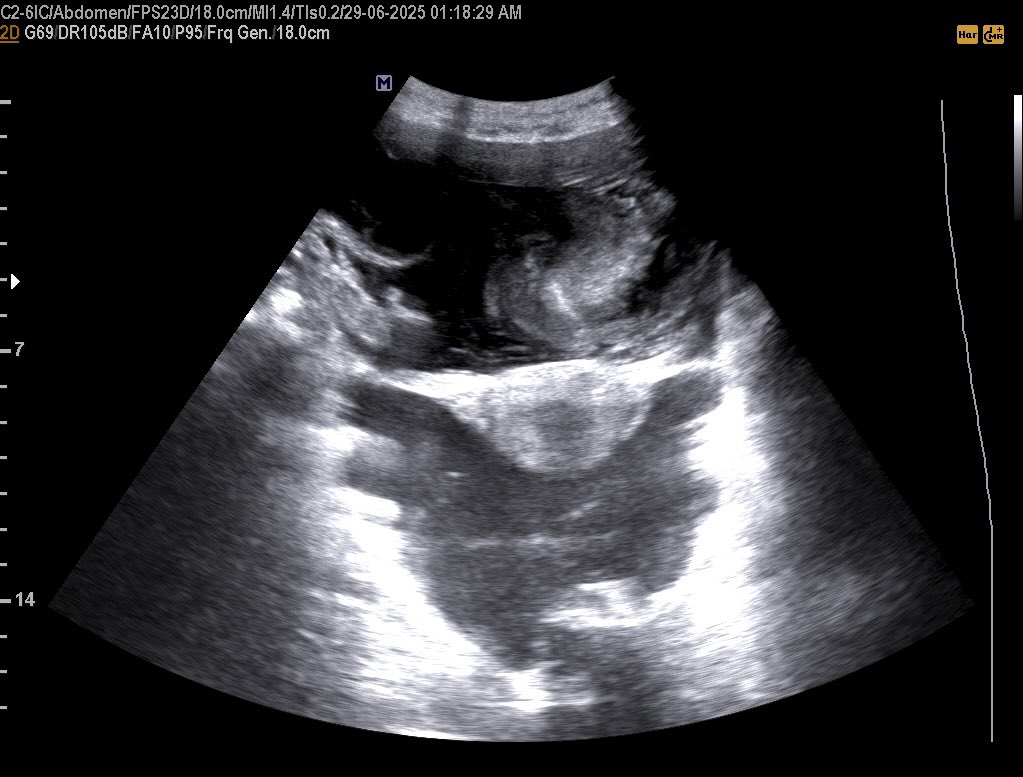

28 years female presented with non-specifc abdominal pain. This mass seen just posterior to the Stomach and left lateral to the abdominal aorta , your opinion? #EchoTech